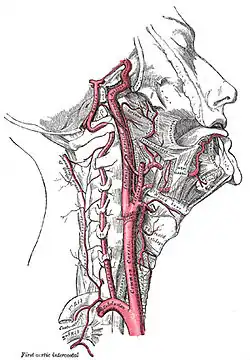

Vier große Schlagadern versorgen das Gehirn des Menschen und der meisten Säugetiere mit sauerstoffreichem Blut (alte Bezeichnung: „arterielles Blut“). Je zwei liegen auf jeder Seite des Halses, vorn die inneren Halsschlagadern (Arteriae carotides internae) und hinten die Wirbelarterien (Arteriae vertebrales). Das Blut fließt nach der Passage des Gehirns über besondere venöse Hirnblutleiter (Sinus durae matris) ab, die gegenüber den Venen einige Besonderheiten aufweisen.

Vorderer Kreislauf

Den Hauptbeitrag zum arteriellen Zustrom tragen die rechte und linke innere Halsschlagader (Arteria carotis interna dextra et sinistra), die aus der gemeinsamen Halsschlagader (Arteria carotis communis dextra et sinistra) jeder Halsseite entspringen. Die Halsschlagader wiederum ist einer der großen Abgänge aus dem Aortenbogen. Ihr Puls kann leicht vor dem Kopfwendermuskel (Musculus sternocleidomastoideus) getastet werden.

Die rechte und linke Wirbelarterie (Arteria vertebralis dextra et sinistra), die aus den Schlüsselbein-Schlagadern (Arteria subclavia) entspringen und entlang der Halswirbelsäule verlaufen, haben einen geringeren Durchmesser als die Halsschlagadern. Sie treten dabei durch Öffnungen der Querfortsätze der oberen sechs Halswirbel. Die beiden Wirbelarterien gelangen durch das Foramen magnum in die Schädelhöhle und vereinigen sich auf Höhe der kaudalen Brücke zur unpaaren Arteria basilaris.